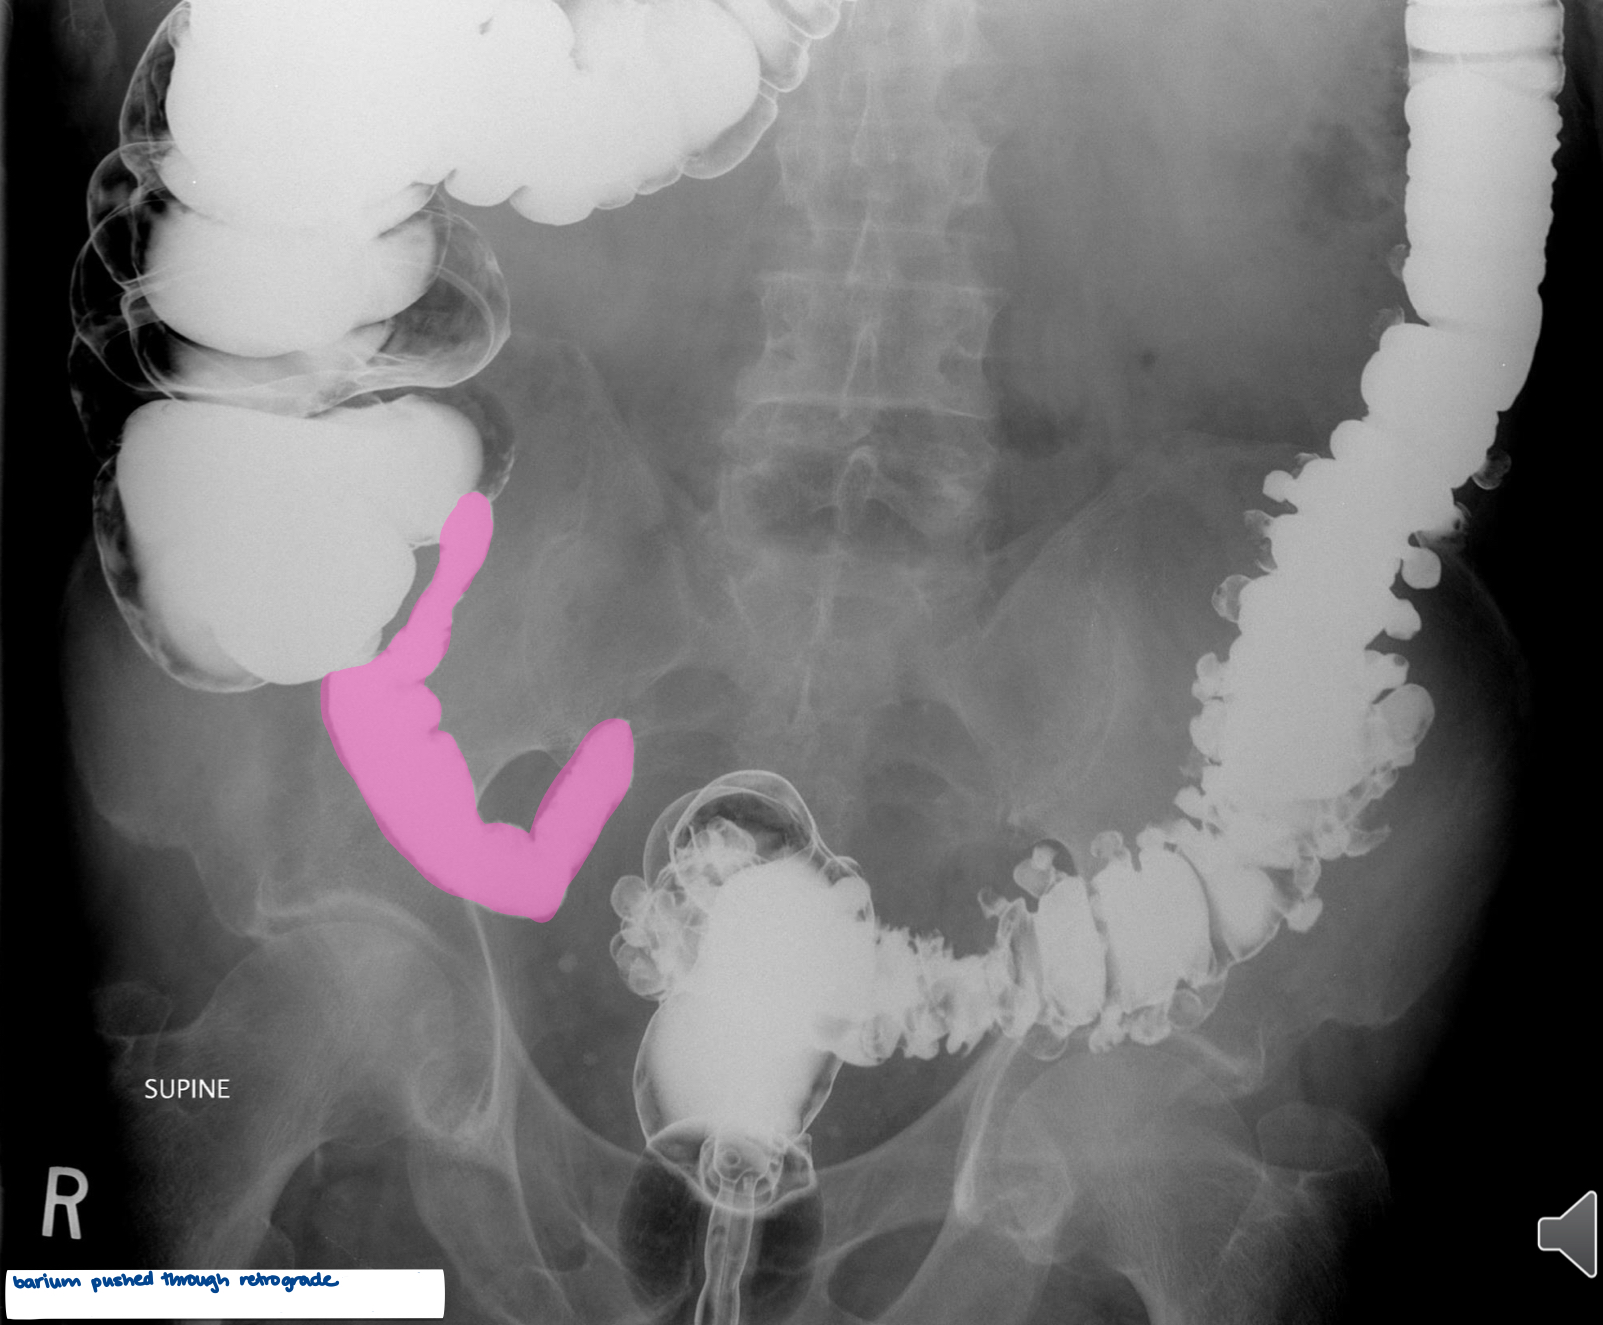

What is the pink area?

terminal ileum